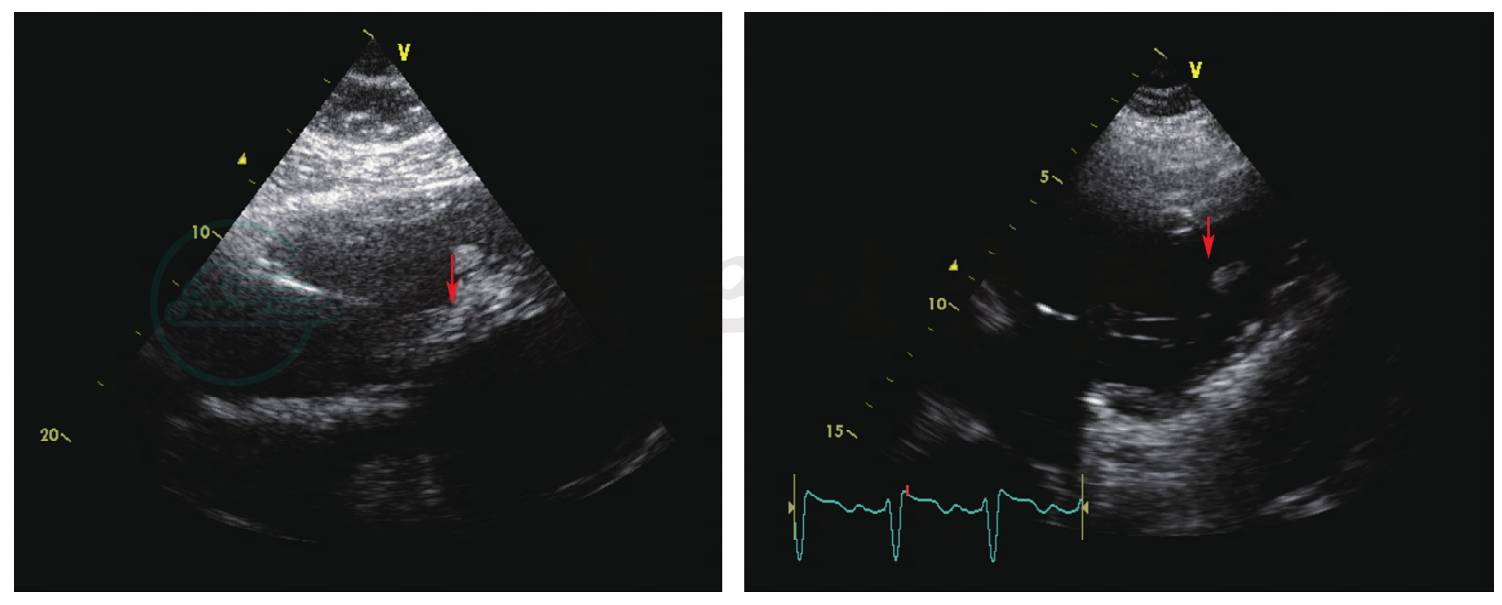

图2 27月26日 (左图)、27日 (右图)复查超声心动图

三尖瓣瓣尖附着团块减小 (箭头所示)